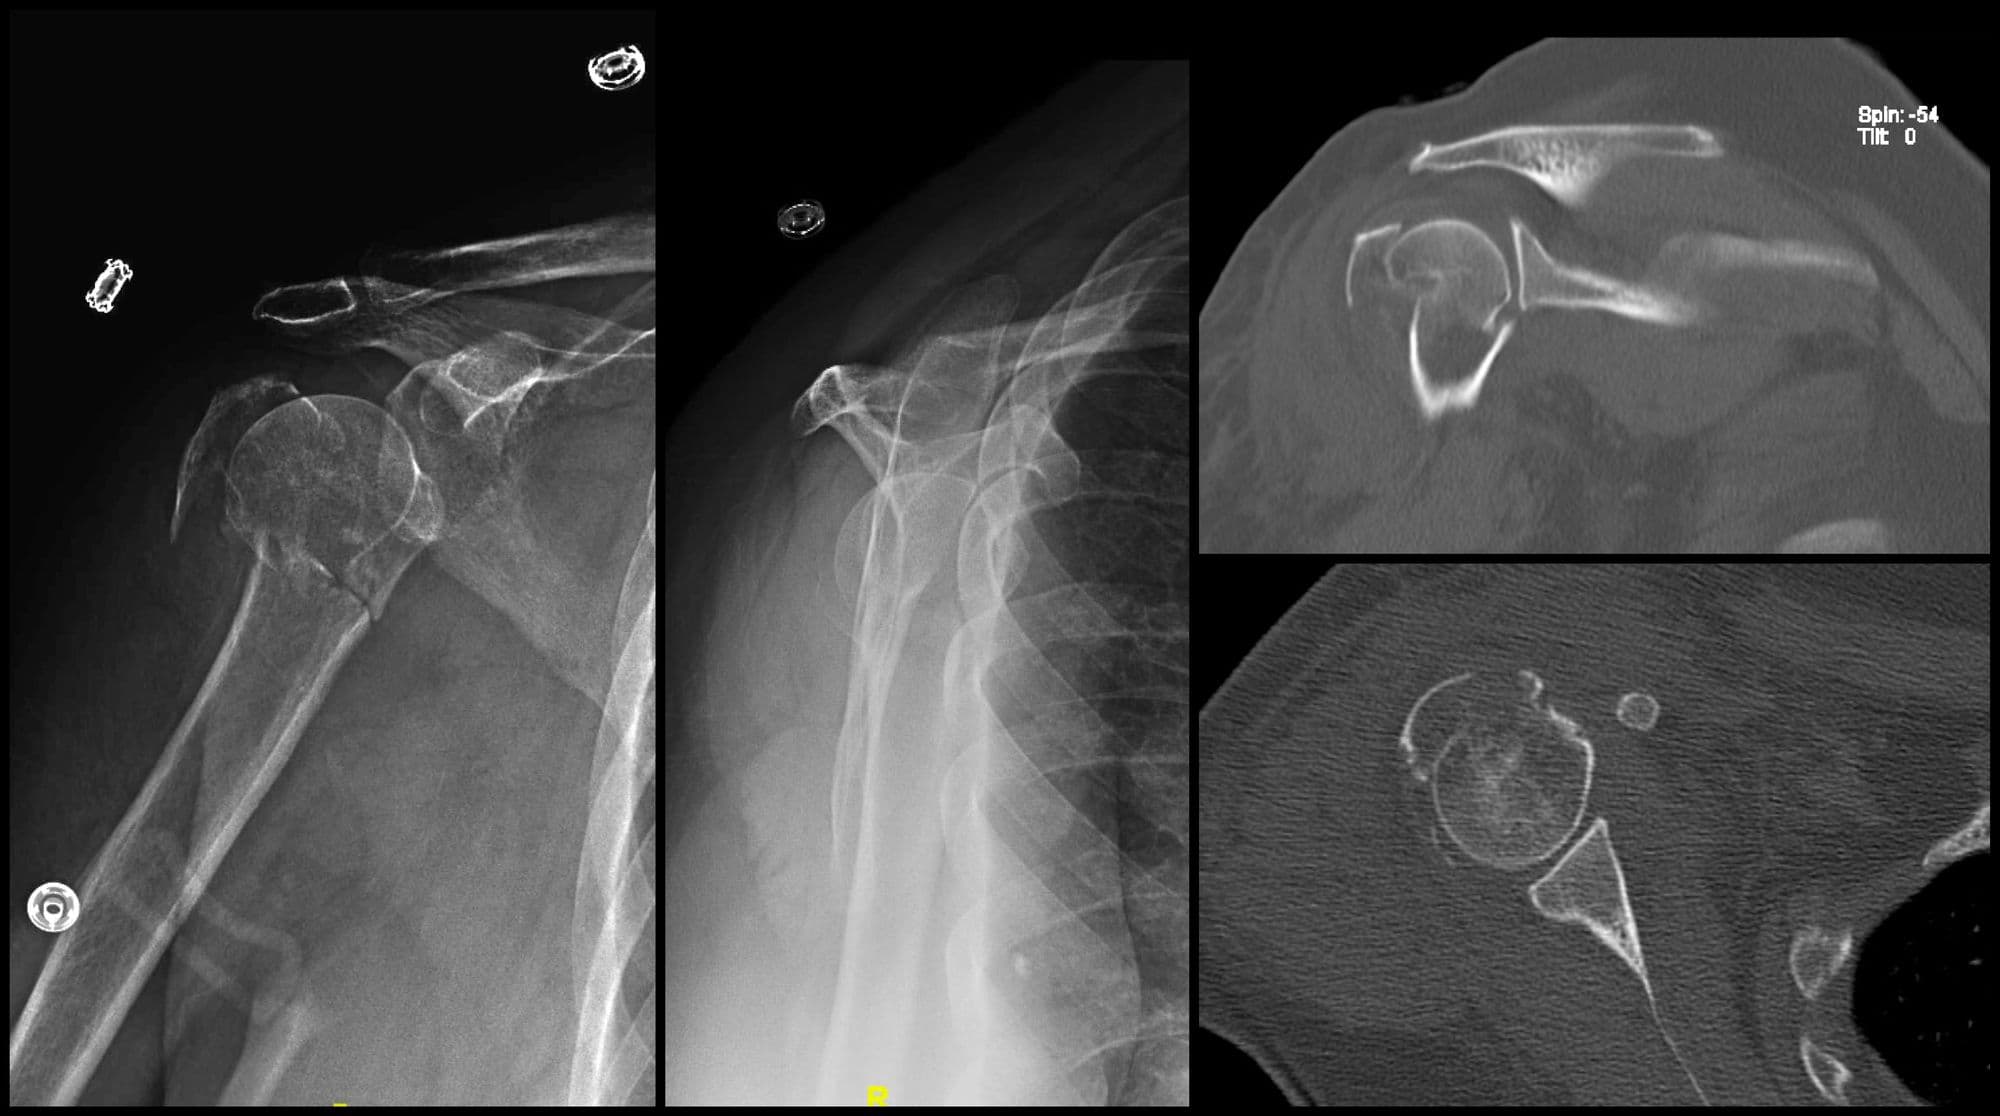

Segmental Humerus ORIF

Imaging

Post-op